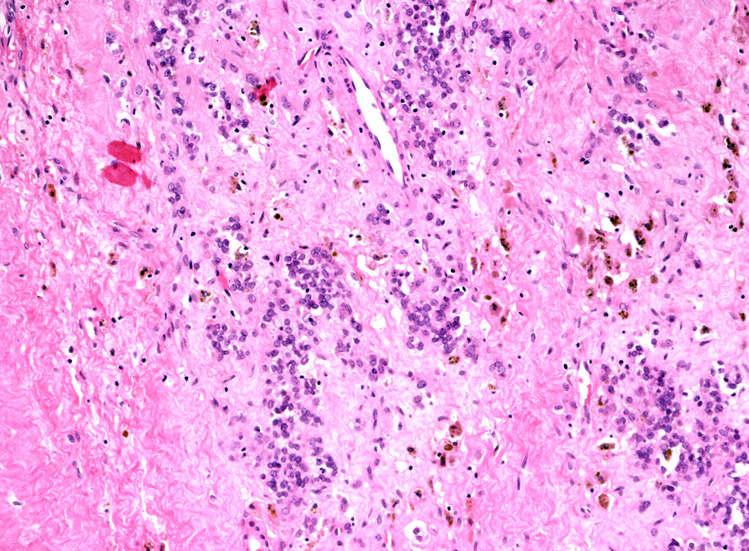

ルーペ像では(Fig.01)ヘモジデリンを貪食したマクロファージに富む線維性間質をもち、腫瘍細胞が胞巣状, 地図状に増殖している。線維性間質はdesmoplasticではなく成熟した線維組織のようである。本例ではさらに腫瘍胞巣内にタンパク液の貯留した偽嚢胞様構造が散在するほか、層状の腫瘍細胞に裏装された嚢胞様構造が出現している。(Fig.03,04)

腫瘍細胞はシート状密に増殖する、類円形小型淡明な核をもった細胞質の乏しい細胞からなる。細胞分裂像は目立たなかった。(Fig.05,06), 線維間質部分の拡大所見。腫瘍細胞が小さな集簇をつくって浸潤している。(Fig.07) Fig08では血管周囲性ロゼットが認められる。